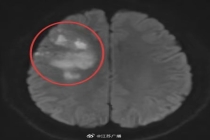

29岁230斤小伙一觉醒来突发脑梗 肥胖与不良习惯埋下隐患

小潘今年29岁,平时饮食不节制且缺乏运动,还有吸烟的习惯,体重达到了115公斤。最近,他在早晨起床时突然感到头痛、视物模糊和口角歪斜。经过医院检查后发现,他患上...